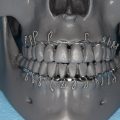

Both an otolaryngology consult and a bolster dressing application have been found to prevent recurrence ( Fig. 2 ).